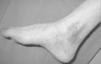

El seguimiento a la largo plazo de las fracturas del astrágalo identifica que la causa más común de los resultados pobres está asociada con la OA subastragalina, tibioastragalina y talonavicular, tanto en nuestra revisión, que alcanzó al 21% (8) de los casos (figs. 9 y 10), como en otros trabajos revisados15,17,19,22,23.

Fig. 9. --A) Fractura del cuerpo del astrágalo tipo B más rotura completa de los 3 ligamentos laterales del tobillo. B) Abordaje bilateral. Osteosíntesis. Sutura de ligamentos. Radiografía y tomografía computarizada a los 18 meses. Artrosis subastragalina y tibioastragalina.

Fig. 9. --a: Type B fracture of the astragalus with complete rupture of the 3 lateral ankle ligaments. b: Bilateral approach. Osteosynthesis. Ligament suture. Radiography and CT at 18 months. Sub-astragalar and tibio-astragalar arthrosis.

Fig.10. --Resultado a los 32 meses. 50° de BA. NAV del cuerpo y artrosis subastragalina y tibioastragalina

Fig.10. --Results at 32 months. BA 50º. Avascular necrosis of the astragalus and sub-astragalar and tibio-astragalar arthrosis.